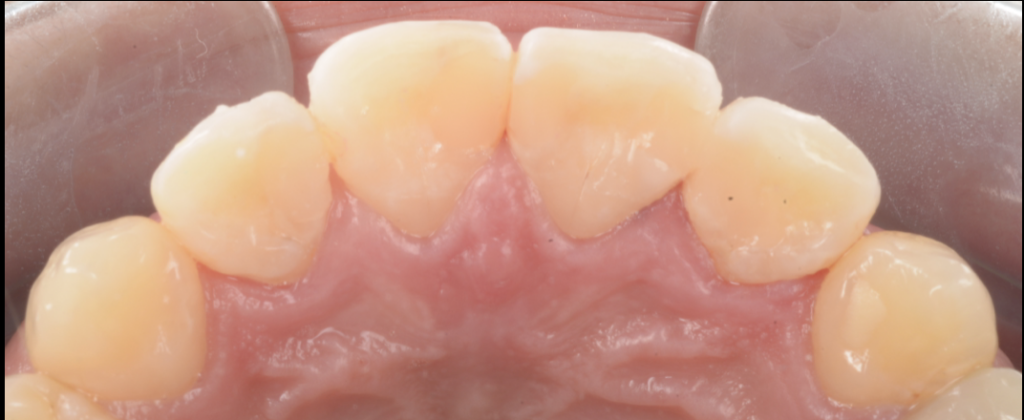

「詰めてあるのに虫歯が進む」理由|接着破綻=細菌の通り道になる

詰め物が入っていると、多くの方は「塞がれている=安全」と感じます。

しかし、接着界面に微細な隙間ができると状況は変わります。

- マージンがわずかに開く

- 微小漏洩(マイクロリーケージ)が起こる

- 細菌が侵入し、修復物の下で増殖する

- 外からは見えにくい場所で感染が進む

- 再治療時に初めて“歯の大半が失われている”ことがある

今回も、色の違和感をきっかけに精査し、修復物を外してみると、想定以上に内部で感染が広がっていました。

なぜラバーダム防湿を行うのか|象牙質に“新しい細菌を入れない”ため

象牙質は体内組織で、水分とコラーゲンを含み、エナメル質と性質が異なります。

唾液や湿気で汚染されれば、接着は不安定になり、再発リスクが上がります。

そこで当院では症例に応じて、ラバーダム防湿を用いて治療環境を整えます。

ラバーダムは、単に乾かすためではなく、

- 汚染を防ぐ(細菌を入れない)

- 視野を安定させる

- 接着の化学反応を“成立しやすい環境”に近づけるために重要です。

接着は“科学”|時間と手順が結果を決める

CR修復は、化学反応と物理特性の上に成り立っています。

たとえば重合収縮。硬化時の収縮ストレスは、マージン破綻や微小漏洩の原因になり得ます。

そのため臨床では、積層充填や硬化手順などを工夫し、ストレスを分散させます。